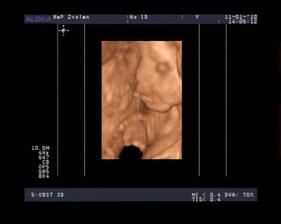

- 19.2.10 sono v 30tt , pani doktorka nas pozrela od hlavy po paty a vsetko je tak ako ma, skontrolovala aj prietoky a su na vybornu a vazime 1670g a

mame na 100% potvrdene DIEVČATKO 🙂.....